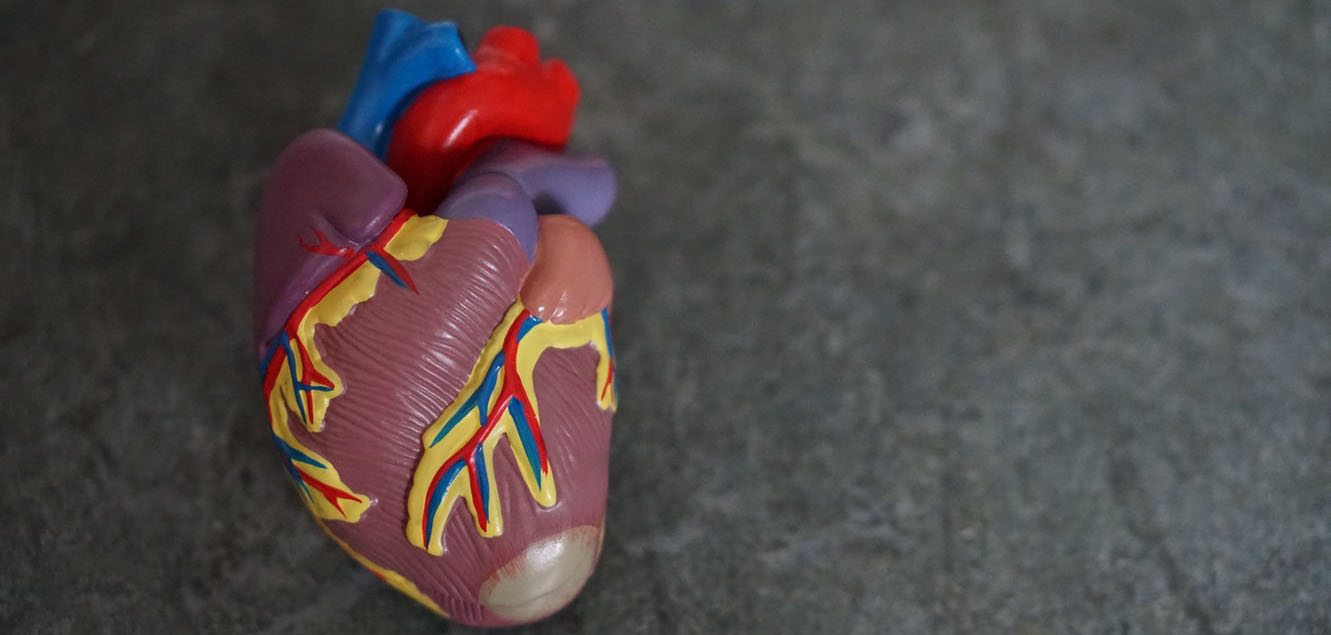

Welcome to

Heart HospitalAssiut University

Welcome to

Heart HospitalAssiut University

مستشفى القلب الجامعي جامعة أسيوط هي أكبر مستشفى في صعيد مصر لعلاج امراض القلب. حيث انها تستقبل الاف المرضي شهريا لتلقي العلاج والفحص واجراء العمليات العديدة من جميع انحاء الجمهورية حيث انها تتميز بوجود نخبه من أساتذة جراحه القلب في جميع تخصصات جراحات القلب المتعددة. نرحب بحضراتكم في أكبر صرح لجراحات القلب في صعيد مصر ونتمنى لحضراتكم الشفاء العاجل